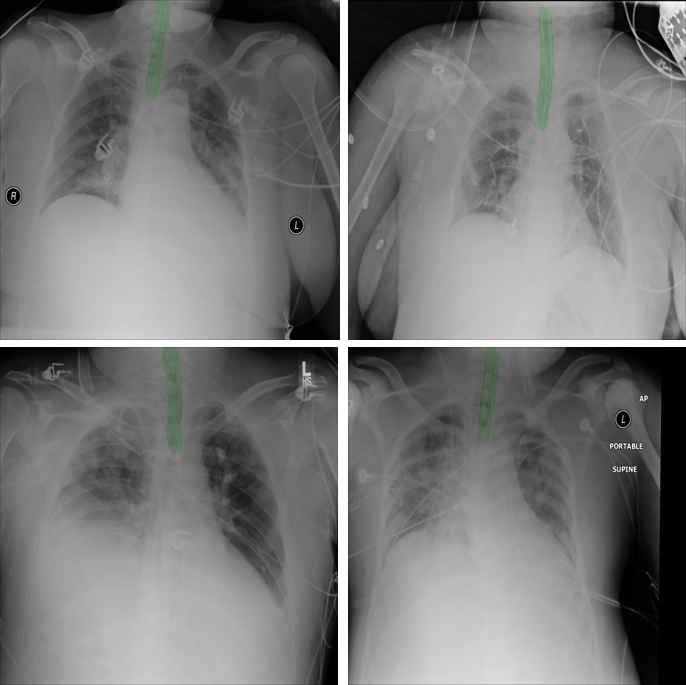

Refer to caption

Figure 2: Original X-ray images (left column), Clavicles segmentation and synthesized ET tube (middle column) and Synthesized ET tubes blended into the original X-ray (right column)

Generating the synthetic ET tubes over real X-ray images includes the following main steps as shown in Fig. 2: a) Selection of cases from the NIH dataset that do not contain ET tubes but may include other tubes (such as nasogastric (NG) tube, drainage tubes, catheters); b) Segmentation of the clavicles in order to localize the synthetic ET tube in the trachea area; c) Blending of generated synthetic ET tubes onto real X-ray images.

The last step for creating a realistic X-ray with an ET tube is to merge the synthetic tube with the real X-ray image. We selected AP X-ray images from the NIH dataset that do not contain ET tubes and blended the random synthetic ET tubes into the images. We used a simple blending with random weights in the range of [0.1,0.2]0.10.2[0.1,0.2].